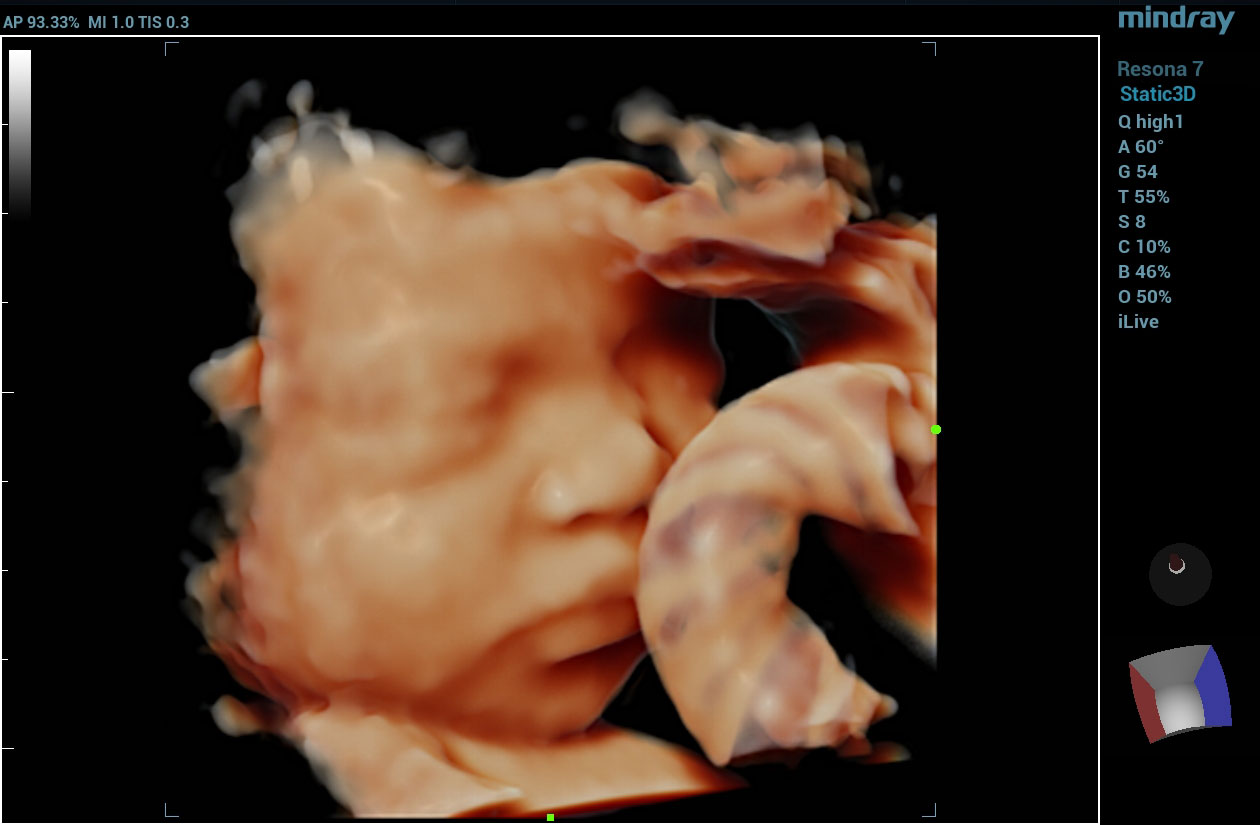

To address the changing needs of today’s value-based care environment, the Resona 7 Ultrasound System Platinum Edition was developed to capture clear, uniform images for radiology, vascular, women’s health, pediatric, and shared service imaging applications.

Premium imaging coupled with advanced workflow technologies help ease clinicians’ increasing workload by offering intuitive and easy-to-use smart tools and AI-enhanced technologies to elevate clinician and patient satisfaction. The user-directed ergonomic design is ideal for daily use, enabling clinicians to capture premium images without sacrificing comfort.